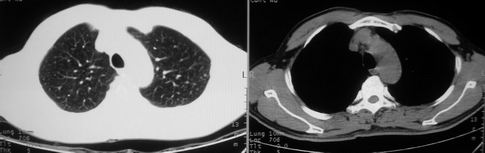

男,62岁,咳血两天。无其他不适。

右肺上叶浅淡密度增高影,考虑炎性病变

像多个结节聚集在一起的病变,且密度较淡  首先考虑为结核吧  建议密切复查

片状磨玻璃影,考虑肺泡出血可能性大,其他不排除,建议hrct

右上磨玻璃样密度影,考虑就是个肺泡出血,别的没有

病灶呈“磨玻璃影”,较薄,周围无卫星灶,很难一口说是肺结核,建议积极治疗后,短期复查!(支持考虑:肺泡出血!)

右肺上叶可见多发磨玻璃状影,符合肺泡内出血表现,严格意义上讲应该是肺泡内积血。引起出血的原因很多,不一定非得结核所致。